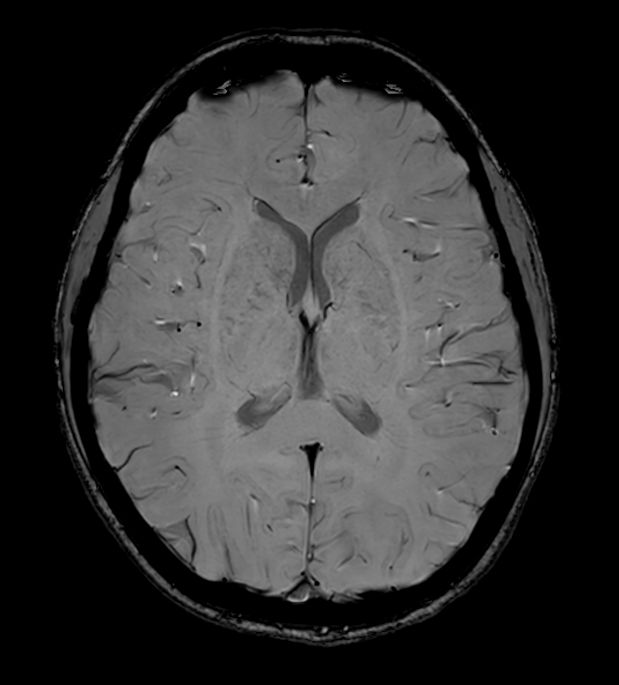

Sagittal 3D Double IR

-

3D Double IR (Axial reformat)

3D Double IR (Coronal reformat)